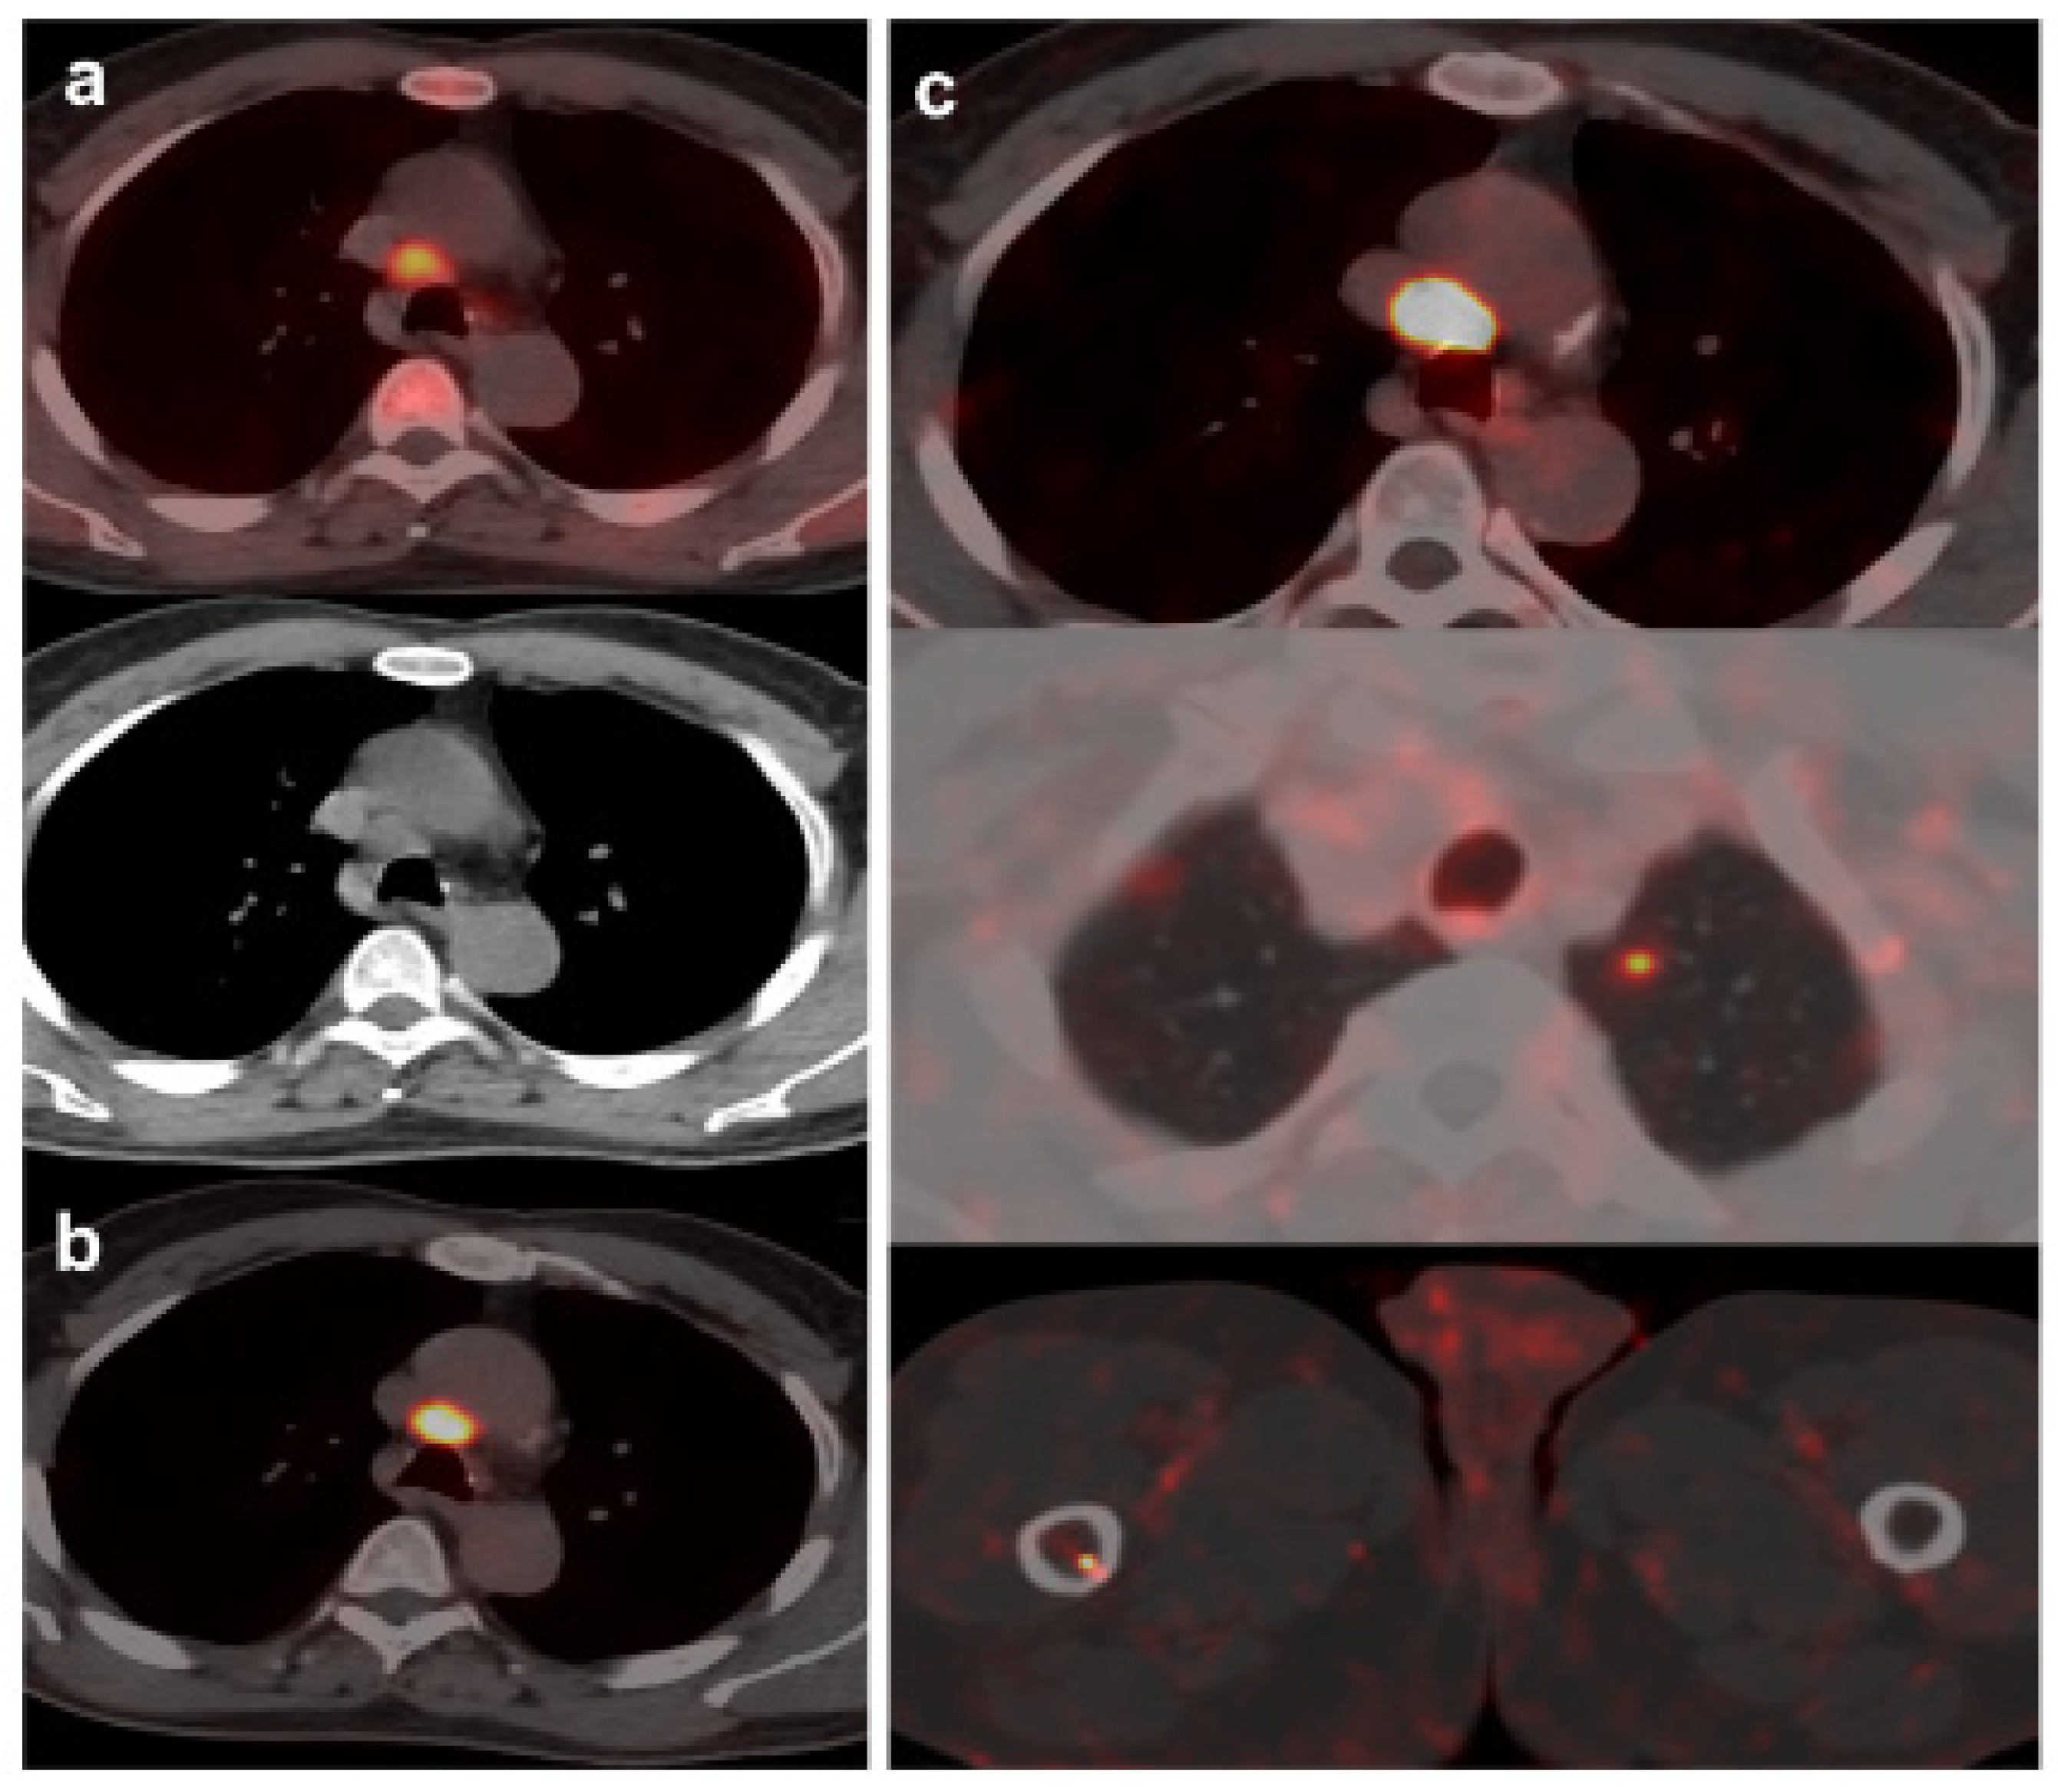

Figure 3. 55-year-old patient. Gleason 8 PCa treated with RP. First BCR treated with prostate fossa radiotherapy. Second BCR (PSA: 0.84 ng/mL, PSAdt 5.99 mo, PSAvel 0.07 ng/mL/mo). 18F-Fluorocholine-PET/CT negative (a). 18F-DCFPyL-PET/CT (b), time window of twenty days, revealed two right external iliac lymph node metastasis (arrows). Lymphadenectomy was decided (escalation), without histopathological confirmation of malignancy. In follow-up PSA progressed (2.07 ng/mL) and an additional 18F-DCFPyL-PET/CT (c) showed exactly same lymph nodes (arrows). SBRT was administered decreasing the PSA level, reclassifying 18F-DCFPyL-PET/CT results as true positive.